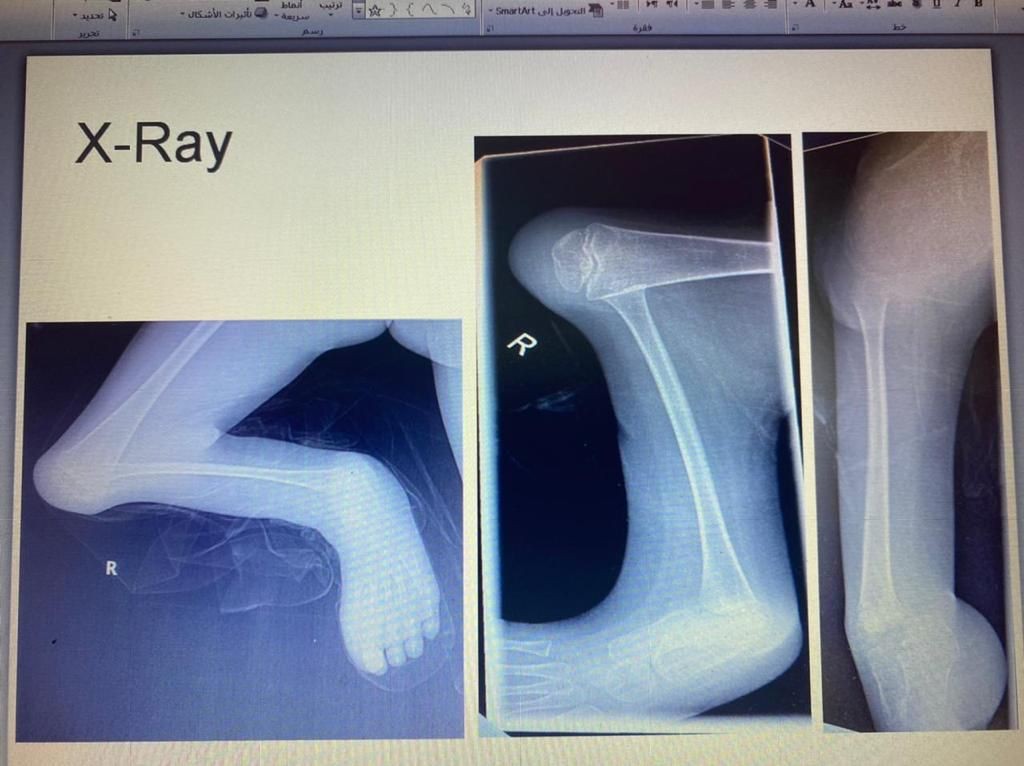

نجح الفريق الطبي في قسم جراحة العظام بمستشفى الملك فهد العام بجدة بقيادة الدكتور عبدالهادي العمودي من إجراء عملية جراحية لطفل بعمر 8 اعوام في ساقه اليمنى تحديداً بعظمة القصبة الرئيسية وإيجاد عظمة شظية ثانوية بالساق اليمنى.

وبعد عمل الفحوصات الطبية اتضح أن الطفل يعاني من تشوه خلقي لفقدانه عظمة القصبة بالساق اليمنى وتم  قيام الفريق الطبي بإجراء عملية جراحية تكميلية لعظمة الشظية بالساق لتعويض القصر في العظمة، وتمكن الأطباء بعملية توفير عظمة الشظية من عظمة الفخذ باستخدام جهاز الاليزروف وتم تعديل القدم تحت عظمة القصبة بالشظية وإدراج القدم تحت عظمة الشظية.

ثم بفضل الجهود المتواصله من قبل الفريق الطبي المتمكن تكللت العملية الجراحيه بنجاح ولله الحمد وعودة الساق إلى شكلها الطبيعي بعد أن كانت العظمة مفقودة.